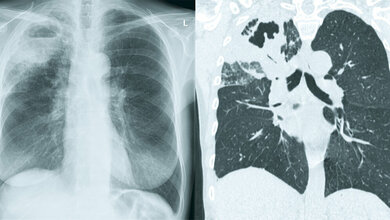

Zwei dieser Verpflichtungen beruhten auf der Diagnose einer Tuberkuloseinfektion und -erkrankung: Bereitstellung einer Tuberkuloseprophylaxe für mindestens 45 Millionen Menschen zwischen 2024 und 2027 und Erreichen von 90 % der geschätzten Zahl von Tuberkuloseerkrankten durch qualitätsgesicherte Diagnose und Behandlung zwischen 2023 und 2027. Diese Verpflichtungen stehen im Einklang mit der End-TB-Strategie der Weltgesundheitsorganisation (WHO). Diese fordert die Erkennung von Tuberkulosepatienten mit einem höheren Risiko einer Entwicklung zu aktiver Tuberkulose, damit sie eine Tuberkuloseprophylaxe erhalten können. Darüber hinaus soll Tuberkulose und medikamentenresistente Tuberkulose (DR-TB) durch einen universellen Medikamentenempfindlichkeitstest (DST) frühzeitig diagnostiziert werden. Diese globalen Verpflichtungen und Pläne unterstreichen laut WHO die entscheidende Rolle von TB-Tests für den schnellen und genauen Nachweis von TB-Infektionen, -Erkrankungen und -Resistenzen.

Um die Länder bei ihren Bemühungen zur Verbesserung der Erkennung von TB-Infektionen, -Erkrankungen und -Resistenzen zu unterstützen, veröffentlicht das Globale TB-Programm der WHO evidenzbasierte politische Leitlinien zu TB-Teststrategien und -technologien. Diese Leitlinien werden regelmäßig aktualisiert. Seit der Veröffentlichung der jüngsten konsolidierten Leitlinien zur TB-Diagnose im Jahr 2024 lagen nun neue Erkenntnisse zur Anwendung der von der WHO empfohlenen Schnelltests (WRD, WHO-recommended rapid diagnostic tests) zum Erstnachweis von TB und Rifampicin-Resistenzen in Bevölkerungsgruppen mit erhöhtem Risiko für TB-bedingte Morbidität und Mortalität (z. B. HIV-Infizierte und Kinder) vor. Daneben wurde eine systematische Evidenzbewertung zu molekularen WRD (mWRD), die zuvor als eigenständige Produkte empfohlen wurden, abgeschlossen, um die Einordnung der mWRD in bestehende oder neue Klassen von TB-Diagnosetechnologien zu bestimmen. Außerdem ging ein Aufruf aus den Ländern ein, die Leitlinien zu TB-Infektionen, -Erkrankungen und Arzneimittelresistenztests in diesen konsolidierten Leitlinien zur TB-Diagnose zusammenzufassen, um die Umsetzung nationaler Testprogramme zu optimieren. Als Reaktion darauf sei die vierte Auflage der konsolidierten Leitlinien zur TB-Diagnose veröffentlicht worden.

Im Vergleich zur dritten Auflage (erschienen 2024) ist diese Leitlinie die erste, die die Leitlinien der WHO zur Diagnose von TB-Infektionen, -Erkrankungen und Arzneimittelresistenzen in einem einzigen Referenzdokument zusammenfasst. Darüber hinaus etabliert sie zwei neue Klassen von TB-Diagnosetechnologien (für den Erstnachweis von TB und Rifampicin-Resistenz) und gibt neue Empfehlungen zur gleichzeitigen Untersuchung von respiratorischen und nicht-respiratorischen Proben bei Erwachsenen und Jugendlichen mit HIV, Kindern mit HIV sowie Kindern ohne HIV oder mit unbekanntem HIV-Status.